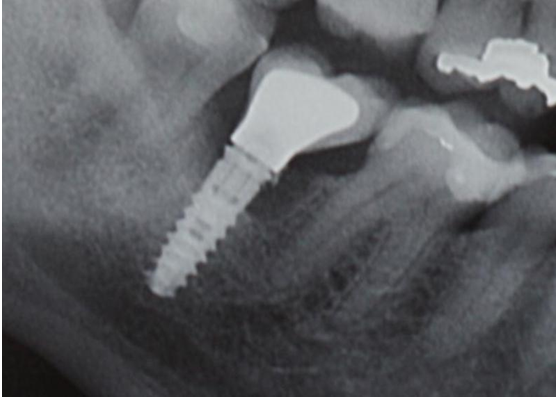

6. Εμφυτεύματα στην πρόσθια περιοχή (αισθητική ζώνη)

Στην ασθενή οι τομείς στην άνω γνάθο είχαν χαθεί λόγω τερηδόνας. Στην περιοχή τοποθετήθηκαν δύο εμφυτεύματα και έγινε μία γέφυρα τεσσάρων τεμαχίων (δοντιών) επί αυτών.

Η κλινική εικόνα μετά την τελική αποκατάσταση (γέφυρα) κρίνεται απόλυτα επιτυχής.

Εμφυτεύματα στην πρόσθια περιοχή (αισθητική ζώνη)

Αρχική Φωτογραφία

Τελική Φωτογραφία

Τελική Ακτινογραφία